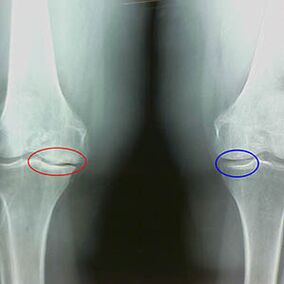

Determining the degree of arthrosis occurs from X -RayDetering participation in the pathological process of bone structures.Their change indicates that the muscle system is in imbalance for 5-10 years.As a rule of peopleThey experience pain in pain for several years.

Early X -Ray Characteristics of the second phase of the knee arthrosis:

- Striking edges of Inter -Crib tubercles on tibia, where the ligament being transmitted is attached;

- narrowing the joint gap on the medial side;

- Sponsed edges of the consile bones on medial sides, less often in lateral - depending on the development of the deformation of common valgus or variation.

For the second phase in LarsenThe narrowing of a common gap for more than 50% is characteristic, but this can only be checked in dynamics or comparison, with a difference from the separated compound.